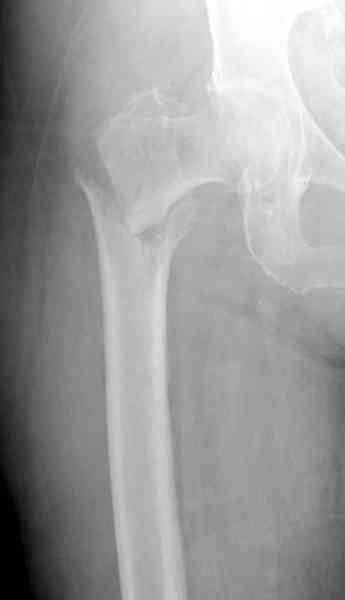

Здесь сканнированные снимки импланта и операционные снимки больной.

Итог